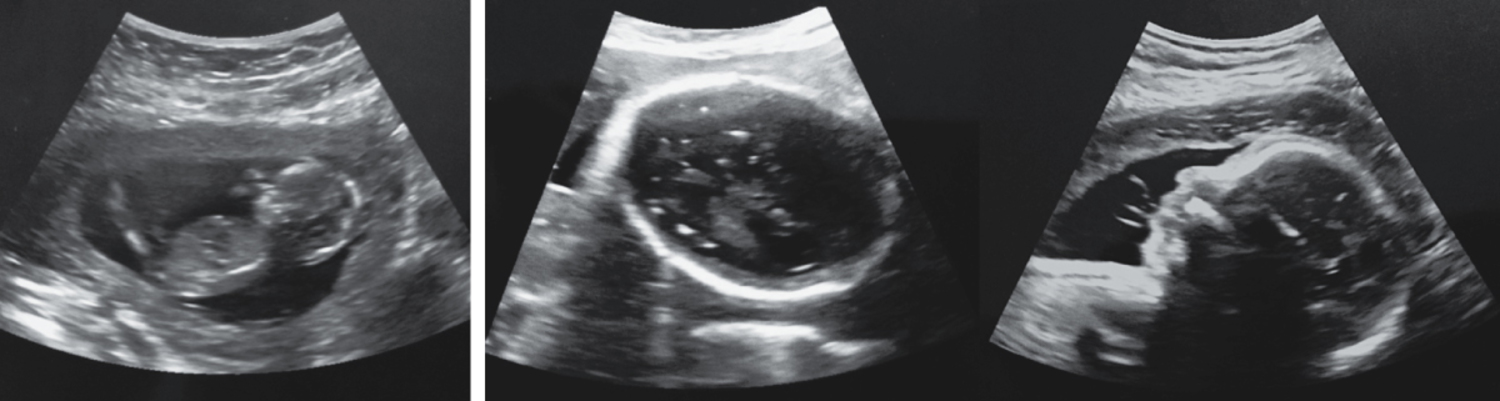

A 6-month-old baby boy was referred to a pediatric neurology clinic in Brazil for evaluation of developmental delay. At the beginning of the second trimester, the baby’s mother had had a rash. At birth, the baby had microcephaly. He subsequently developed severe developmental delay and epilepsy. Prenatal ultrasonography at 12 weeks’ gestation and at 29 weeks’ gestation are shown. What is the underlying etiology?

一名6个月大的男婴因发育迟缓被转诊至巴西的一家儿童神经科门诊进行评估。在怀孕第二孕期初期,婴儿的母亲曾出现过皮疹。婴儿出生时患有小头畸形。随后,他出现了严重的发育迟缓和癫痫。妊娠12周和29周的产前超声检查如图所示。其根本病因是什么?